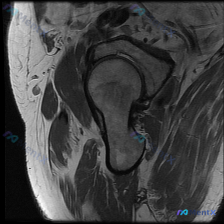

看到一份髋关节MRI T1序列冠状位的病例材料,用户预设想了解盂唇病变的可能性。 先看基础影像分析: - 扫描范围:单侧髋关节区域,包括股骨头、股骨颈、大转子、髋臼及其关节间隙 - T1序列特征:正常骨髓高信号,皮质骨低信号,肌肉中等信号,关节软骨及韧带清晰 - 股骨头/股骨颈:轮廓光滑,未见水肿、...

看到一个髋关节MRI病例,先给大家分享一下核心发现: 影像类型:髋关节MRI冠状位T1加权成像 主要表现:股骨头及股骨颈近端骨髓呈弥漫性T1低信号,与正常脂肪骨髓的高信号形成鲜明对比;髋臼顶轮廓清晰,关节间隙无明显狭窄,盂唇在T1序列上未见明确撕裂征象。 患者主诉提到了“盂唇病变”,但影像核心是骨髓...

最近看到一个髋关节病例,临床怀疑盂唇病变,但提供的单张MRI-T1冠状位影像未发现明确异常。影像显示股骨头形态基本圆滑,与髋臼窝对合良好,骨髓信号均匀,未见明显的骨髓异常或结构破坏。 大家来讨论一下: 1. 这种情况下还需要做哪些检查来明确诊断? 2. 可能的诊断方向有哪些? 3. 单序列MRI的局...

整理到一个髋关节MRI分析的内容,仅提供了单张T1序列冠状位图像,临床关注点是盂唇病变。先看一下这张图像的客观描述: 骨骼结构:股骨头圆形,轮廓光整,骨皮质连续,骨髓信号均匀;髋臼形态连续,骨皮质清晰;大转子区域骨皮质完整。 关节间隙:宽度基本对称,无明显狭窄,无异常信号填充。 软骨与盂唇:股骨头表...

整理到一张髋关节T1加权冠状位MRI的病例资料,初始有人提问「能否观察到盂唇病变」。先放这张图的核心影像描述:图像聚焦一侧髋关节,股骨头形态基本呈圆形,股骨头前上方负重区皮质下可见清晰带状低信号影,其余股骨头、颈骨髓信号为正常脂肪高信号,关节囊无明显增厚或积液。 想问问大家:仅看这张图的描述,您第一...